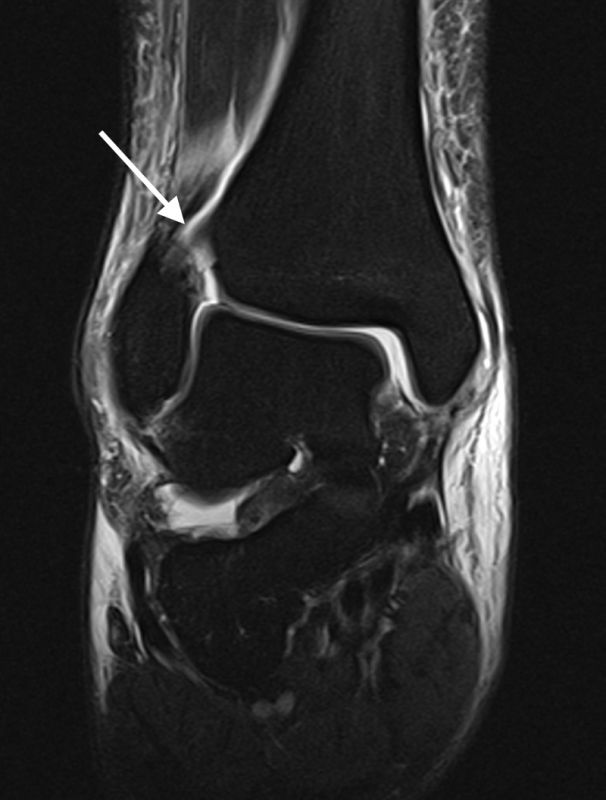

Die Magnetresonanztomographie stellt aktuell den Goldstandard in der Diagnostik von Syndesmosenverletzungen dar (Szeimies 2013). Beschrieben sind eine Sensitivität von 100% und eine Spezifität von 93% bei Verletzungen des AITFL, sowie eine Sensitivität und Spezifität von 100% bei Verletzungen des PITFL. Darüber hinaus ermöglicht das MRT weitere ligamentäre, chondrale oder intraossäre Verletzungen zu detektieren. Bei chronischen Syndesmosenverletzungen sollte eine MRT-Diagnostik mit Kontrastmittel (KM) intravenös durchgeführt werden, da diese eine höhere Spezifität und Sensitivität im Vergleich zur nativen MRT-Bildgebung aufweist. Durch die zusätzliche Gabe von KM können durch eine Mehranreicherung des KM im Bereich der Syndesmose Rückschlüsse auf das Vorhandensein einer chronische Instabilität gezogen werden 41.